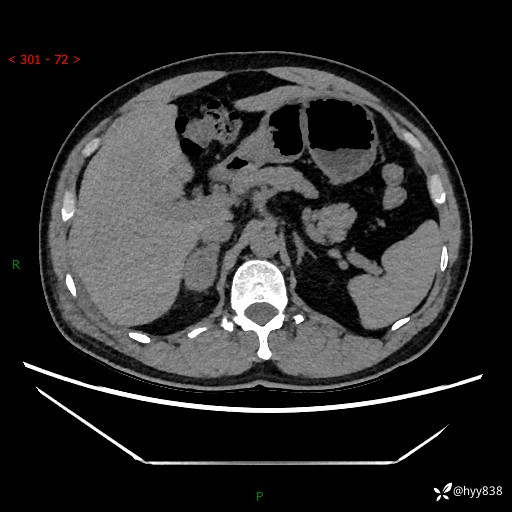

现病史:患者9月4日摔伤在深圳市宝安区中心医院行CT检查提示右侧肾上腺区结节(38*27mm),复查B超提示右侧肾上腺区可见一61*24mm异常低回声团,建议进一步检查。进一步完善增强CT后提示:右侧肾上腺区肿块及周围渗出改变,大致同前,考虑肾上腺腺瘤,不除外瘤内出血可能,否认阵发性头晕、头痛、出汗、乏力等不适,门诊以“ 右侧肾上腺肿瘤”收入住院。 起病来,患者精神、食欲、睡眠可,大便通畅,小便如上述,体力体重无明显改变。

肾上腺CT平扫

增强(动脉期+静脉期)